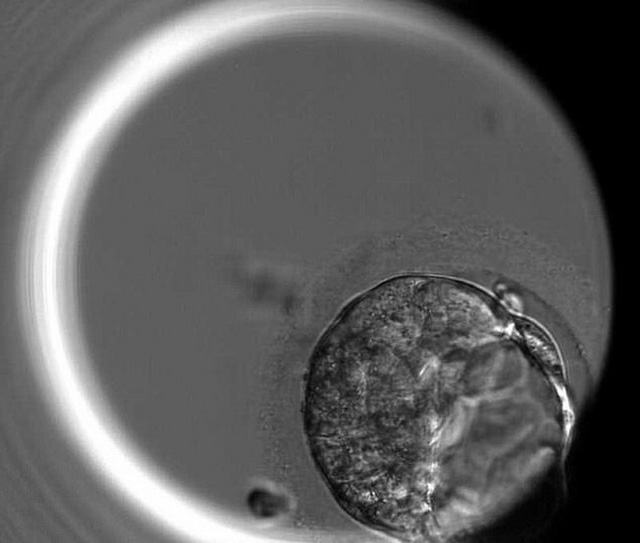

Ảnh chụp một phôi thai 5 ngày tuổi không có protein OCT4, do đó, nó không hình thành được túi phôi – Ảnh: MailOnline

Sau khi trứng đã thụ tinh, nó sẽ bắt đầu tự phân chia cho đến ngày thứ 7, khi đó nó hình thành một quả cầu có chứa khoảng 200 tế bào gọi là "túi phôi", phôi thai cần có protein OTC4 để túi phôi phát triển tốt.

Nếu gene chủ không sản xuất protein OCT4 thì sẽ ảnh hưởng đến việc hình thành túi phôi và dĩ nhiên dẫn đến hư phôi thai.